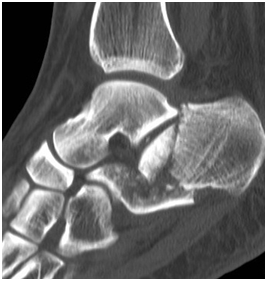

Radiologically

The calcaneus fracture has healed with no Talar shift or tilt (Figure 7-9).

Figure 7 X-Ray of right Ankle: shows no Talar tilt, shift or syndesmotic diastasis.

Figure 8 Lateral view of the ankle: shows the maintained post op position of the tibia and fibula over the talus. The image also shows the healed Calcaneus fracture post ORIF.

Figure 9 Mortise view of the right ankle: shows once again no Talar tilt, shift or syndesmotic diastasis. The ankle joint is congruent.